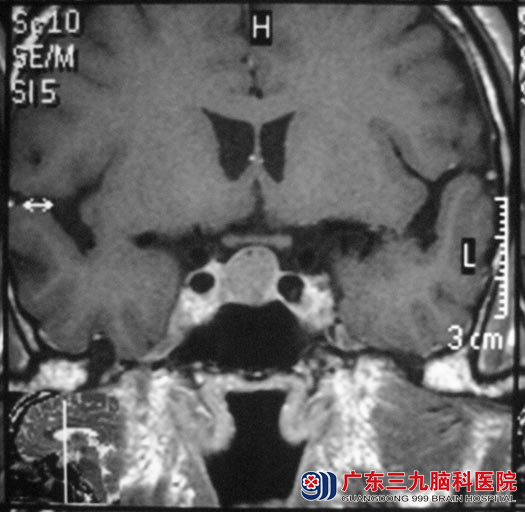

一年前韦先生出现头胀痛,一直未予重视,近日头痛加剧,当地头颅CT检查提示:鞍区占位,广东三九脑科医院头颅MR检查考虑垂体大腺瘤,大小约17.2mm×14mm×16.7mm。

5月28日,垂体瘤诊疗中心 鲁明主任主刀,在导航仪定位下,行经鼻蝶鞍区占位切除术,术前制定导航计划,术中再次导航定位,显微镜下见灰白色肿瘤,血供一般,质软,镜下切除肿瘤,修补鞍底,手术顺利。术后韦先生未出现脑脊液鼻漏、视力视野缺损、尿崩等术后并发症,已康复出院。术后病理结果为:垂体生长激素分泌腺瘤。